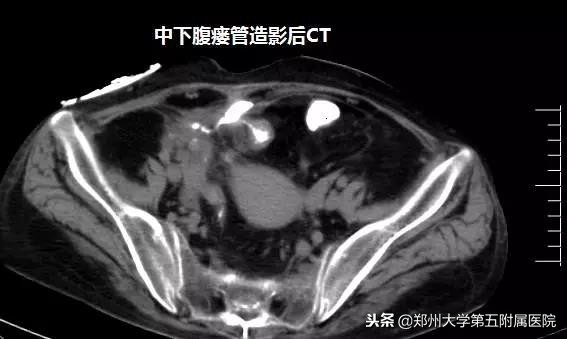

吴万庆副主任医师接诊后,详细了解病史及查体,经过造影及CT检查,确定瘘口的部位及腹腔脓腔情况,发现患者腹壁有三个瘘口,粪便外渗,诊断考虑为克罗恩病并发肠瘘。